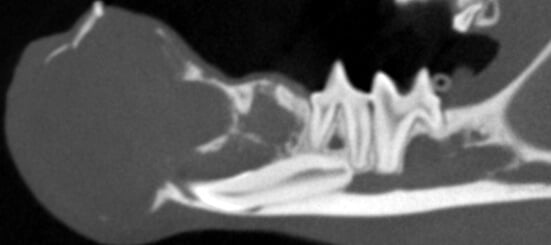

Bilateral rostral mandibulectomy to excise an oral mass that is suspected to be benign (not spreading) but locally invasive. Oral surgical removal of unerupted/impacted lower left canine tooth occupying the majority of the left mandible.

Cystic rostral mandibular swelling associated with unerupted 304. Adopted in Sept as intact male, estimate age 2. RDVM neutered and found mild swelling and unerupted 304 (lower left canine tooth). Swelling increased since adoption.

The canine tooth was not missing, but was impacted present in the middle of the left mandible. A tumor was present requiring removal of the tumor and associated impacted tooth.

We scaled, polished, performed 3D imaging and intraoral radiographs (x-rays), and confirmed the presence of an oral mass. The mass effect appears to have enlarged and extended to the lower right canine tooth.

As previously noted, the lower left canine tooth was unerupted and impacted into the center of the mandible. The cyst growth/mass effect has caused haphazard tissues to be present around all of the incisors.